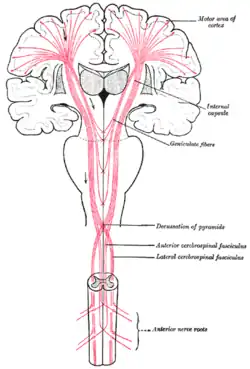

Pyramidenbahnzeichen: Die Pyramidenbahn besteht aus einem Bündel von Nervenzellfortsätzen, die von Stirnhirn bis zu den ersten Umschaltstellen im Rückenmark ununterbrochen durchlaufen. Diese Zellen sind so etwas wie ein Schrittmacher der willkürlichen Bewegungen. Der Name Pyramidenbahn stammt von einer Struktur im Hirnstamm (der pyramis), durch die die Pyramidenbahn hindurchläuft. Wenn dieses Nervenbündel an irgendeiner Stelle unterbrochen wird, kommt es zu einem typischen Funktionsausfall: einer spastischen Lähmung (Kraftminderung mit Muskeltonuserhöhung). Die Ursachen können völlig unterschiedlich sein: Eine Verletzung der Wirbelsäule und des Rückenmarkes, eine Durchblutungsstörung im Hirnstamm, eine Hirnblutung im Bereich der sogenannten Kapsel oder ein Tumor in der Großhirnrinde an der entsprechenden Stelle. Neben der Lähmung und der Muskeltonuserhöhung finden sich dann häufig sogenannte Pyramidenbahnzeichen. Man meint damit in erster Linie das Anheben (Dorsalextension) der großen Zehe beim Bestreichen der Fußsohle an ihrem Außenrand (Babinski-Reflex).

Der junge Mann mit der Kopfplatzwunde hat eine Armlähmung. Anhand der Reflexprüfung kann man feststellen, ob die Lähmung zentral oder peripher ist: Wenn die Muskeldehnungs-Reflexe im rechten Arm abgeschwächt sind, spricht dies für eine Schädigung im Verlauf der Nerven außerhalb des Rückenmarkskanales (periphere Läsion). Wenn die Reflexe betont sind, dann spricht dies für eine Schädigung im Bereich von Rückenmark oder Gehirn (zentrale Läsion).

Ein weiteres Problem stellt das große Artenspektrum dar. Erkenntnisse aus der Humanmedizin lassen sich nur für wenige Erkrankungen übertragen, da andere Säugetiere, Vögel oder gar Reptilien deutliche neuroanatomische und -funktionelle Differenzen aufweisen und das klinische Bild einer bestimmten neurologischen Erkrankung je nach Art erheblich abweichen kann. Selbst ein schwerer Schlaganfall mit komplettem Ausfall des Versorgungsgebiets der Arteria cerebri media, der beim Menschen eine komplette Halbseitenlähmung verursacht, führt bei einem Schaf lediglich zu milden Störungen der Haltungsreflexe, aber kaum zur Beeinträchtigung des Gangbildes. Am auffälligsten ist noch ein Schiefhals, der aber auch viele andere Ursachen haben kann. Dies ist in den Unterschieden hinsichtlich der Kreuzung der Pyramidenbahn und der ganz unterschiedlichen Bedeutung des pyramidalen und des extrapyramidalen Systems für die Bewegungsmuster begründet.